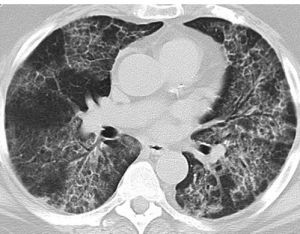

影像學特點:機化性肺炎胸片表現為雙側瀰漫性肺泡影,肺容積正常,復發性和遊走性陰影常見,單側肺泡陰影罕見。高分辨CT顯示肺部斑片狀肺泡腔內實變、毛玻璃影、小結節陰影和支氣管壁的增厚和擴張,主要分布在肺周圍,尤其是肺下野。